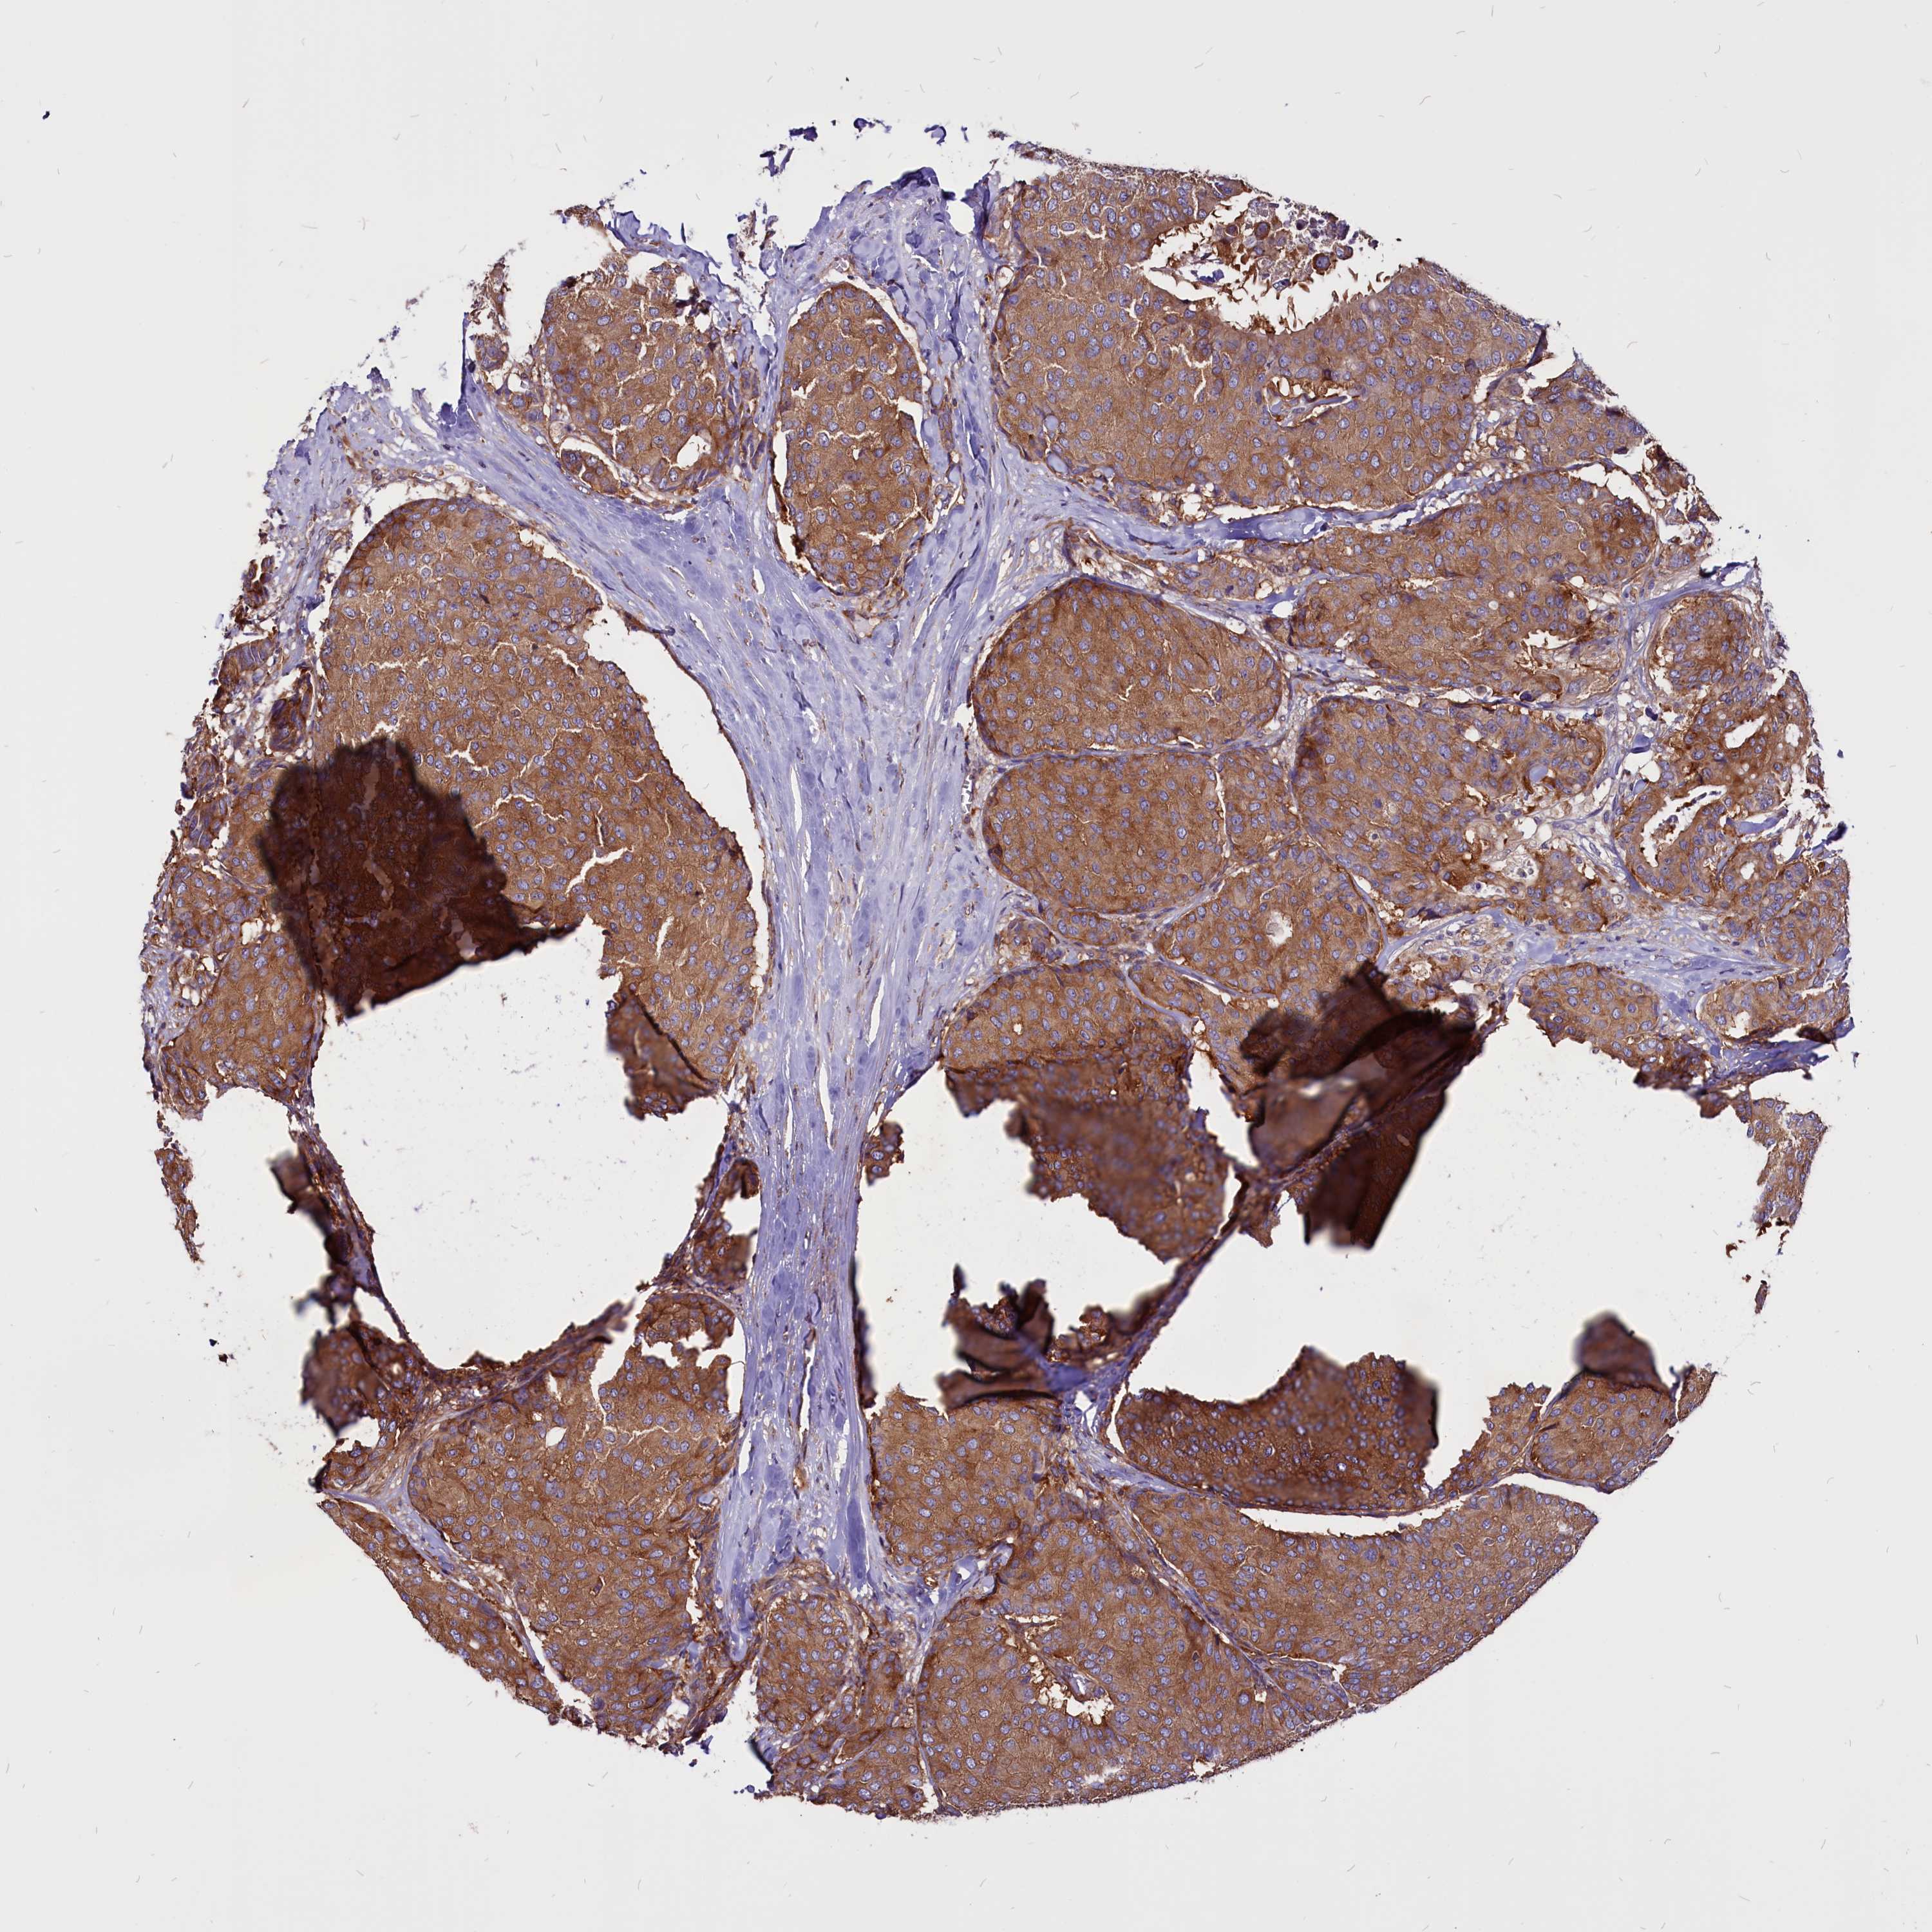

BRCA TCGA BRCA VALIDATION PROTEIN EXPRESSION

Breast cancer

Human cancer